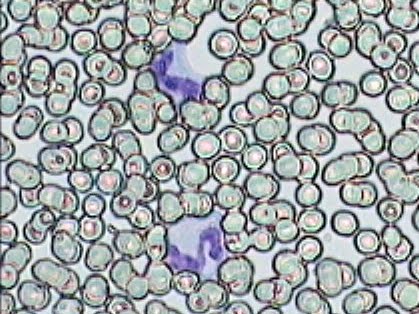

Práctica de Frotis sanguíneo 28